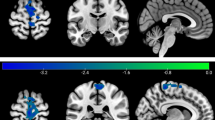

The microstates B (strong activation in the left and right cortices, including BA 17, 18 & right insula) and D (strong activation in the right inferior parietal lobe & right insula (BA13)) revealed significant alterations after yoga training (see Fig. 1c), and the parameter occurrence of the microstate B map decreased from 1.47 Hz (± 0.346) to 0.628 Hz (± 0.510) per second, p = 0.0048. Similarly, microstate D decreased from 0.679 Hz (± 0.443) to 0.154 Hz (± 0.259) after yoga training, p = 0.013. In this study, the temporal coverage (see Fig. 1d) of microstate B decreased from 38.3% (± 15.8%) to 10.5% (± 9.5%), p value = 0.0008. Microstate C (attributed to the posterior cingulate cortex) was associated with an increase in neural activation from 25.2% (± 14%) to 67.7% (± 16%), p value = < 0.0001.

Spatial configuration of MSs and analysis of temporal parameters. (a) Topographic plots of the MSs. (i) Data from before yoga training show cluster maps of A, B, C & D, and (ii) data from after yoga training reveal cluster maps of B, C, D & E. Estimated GEV (b), occurrence (c), time coverage (d), and mean duration (e) from four MSs before and after yoga training. Maps B & D decreased in frequency after yoga training from 1.47 Hz (± 0.346) to 0.628 Hz (± 0.510) (p = 0.048). (Gray color indicates pre-yoga, and orange color indicates post-yoga). The decreased occurrence of MSs may suggest enhanced attention and focus after yoga training among subjects.

Relative power spectral density before and after yoga training (a & b). Frequency domain power topography plots before and after yoga training averaged across all the participants. The power from 5 frequency bins (0–4;4–8; 8–13;13–30;30–45 Hz) before yoga training and after yoga training was averaged over 2 s. The activity distribution before and after yoga clearly differed in the frequency ranges of α, β and γ. (c) The relative percentage changes observed before and after yoga training decreased in the frontal regions at the α,β, and γ frequencies.